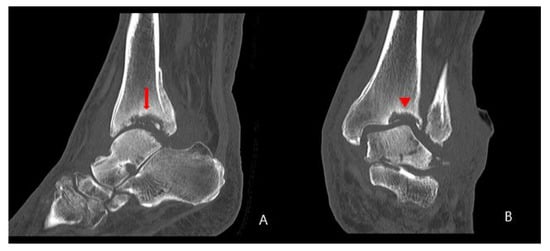

2. Case Presentation

2.1. Preoperative Evaluation